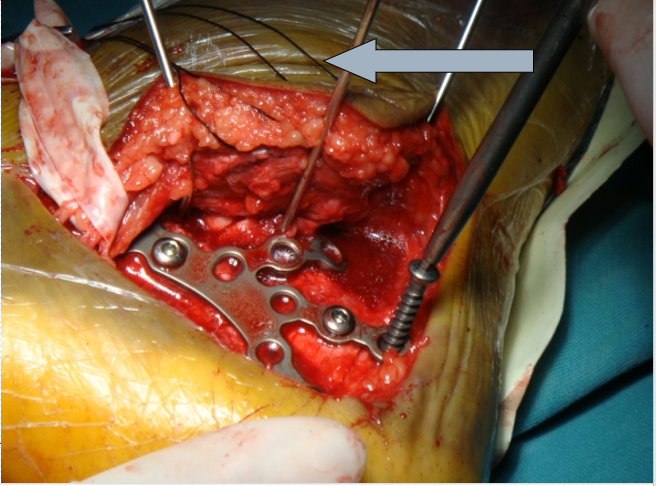

技巧二、切口及显露

外侧切口,可以广泛显露跟骰关节

保护腓肠神经

手术刀要一刀见骨,将骨膜连同软组织以及腓骨长短肌肌腱一起向上掀起。

切开皮肤后开始用7号丝线协助牵开

技巧三、克氏针的位置剥离骨膜后,3根克氏针牵开皮肤。注意距骨前后一根,骰骨一根。这样显露充分